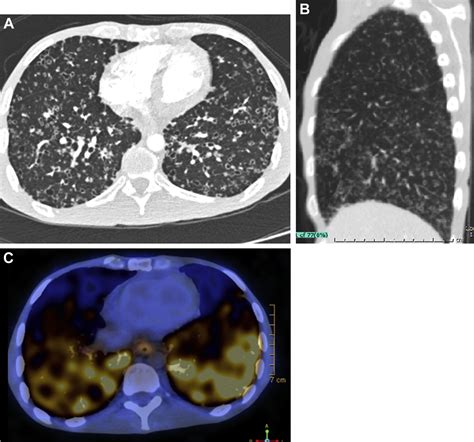

Distinguishing Features on Imaging

Radiologists look for specific markers to help narrow down the diagnosis. The appearance of the cavity's wall, for instance, provides vital clues:

• Thick, Irregular Walls: These are more suggestive of malignancy (e.g., squamous cell carcinoma).

• Thin, Smooth Walls: Often point toward benign causes, such as a congenital cyst or a resolved infection (pneumatocele).

• Air-Fluid Levels: Highly indicative of a lung abscess, suggesting a collection of pus that has not yet been fully drained.